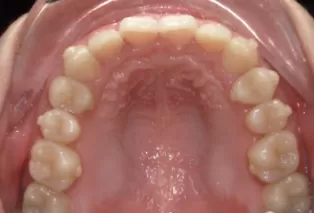

Intraoral photos